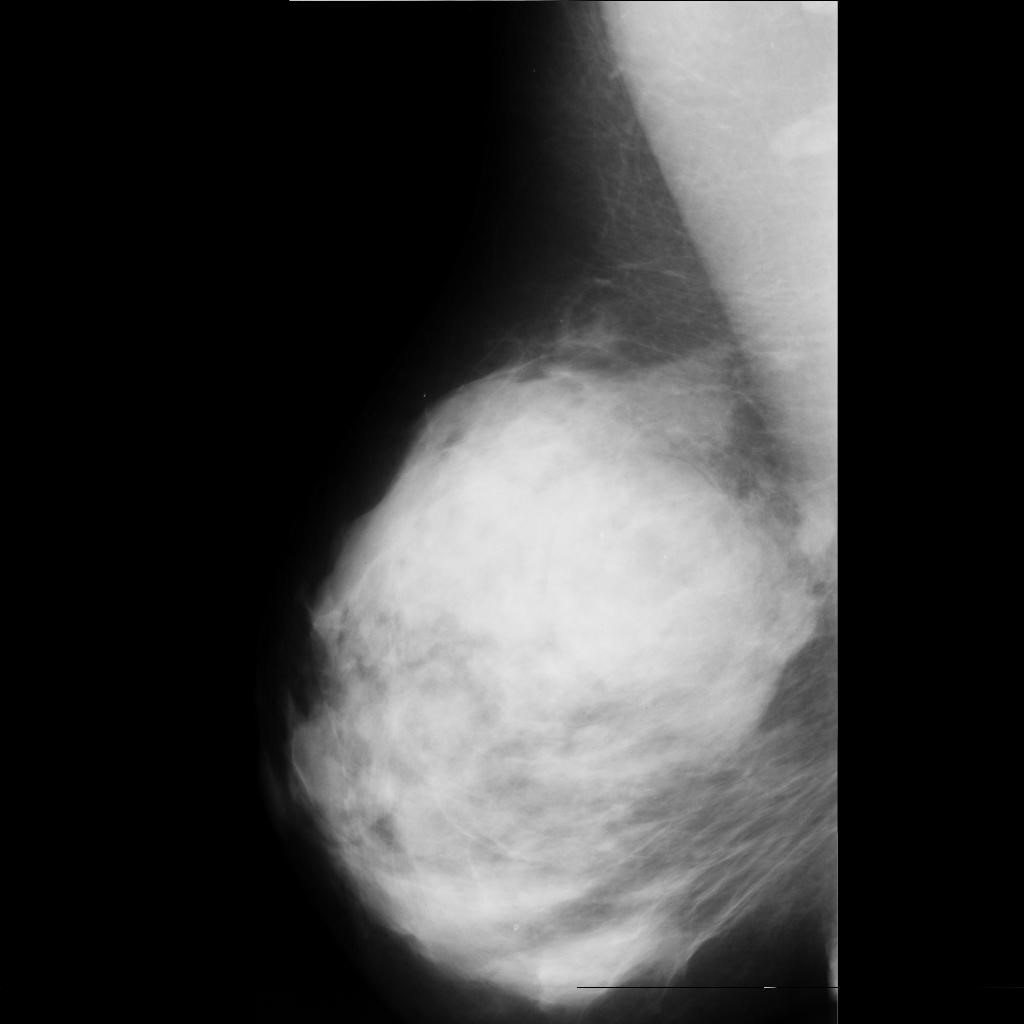

malignant